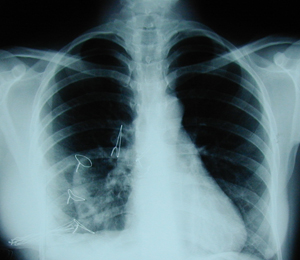

Οπισθιοπροσθία ακτινογραφία θώρακος στην οποία φαίνεται ότι υπάρχει ευμεγέθης όγκος που προβάλλει δεξιά παρακαρδιακά.

Περίπτωση Νο 2

Εικόνα 2

Πλάγια ακτινογραφία του θώρακος. Υπάρχει ευμεγέθης όγκος στην οπισθοστερνική περιοχή, στο επίπεδο της ξιφοειδούς απόφυσης.